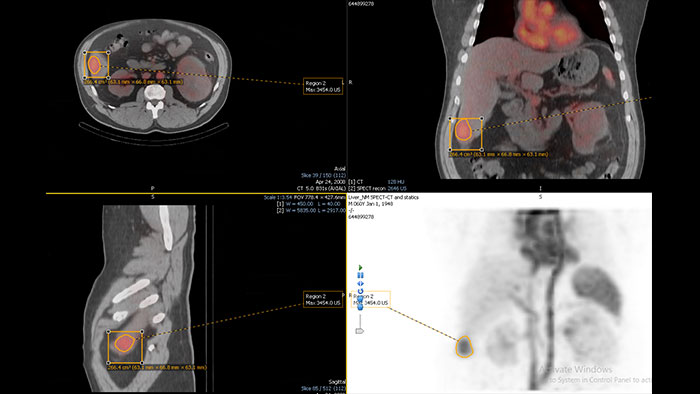

Enhanced user experience for NM reading

Designed to solve your clinical challenges and improve productivity when viewing PET\CT, SPECT, SPECT\CT and planar images. Optimized workflow for handling multiple studies and quantifying findings.

Benefits

NM Review provides a powerful MI and multi-modality image review and analysis environment for clinical evaluation of MI planar, SPECT, SPECT/CT, PET/CT, and PET/MR examinations.